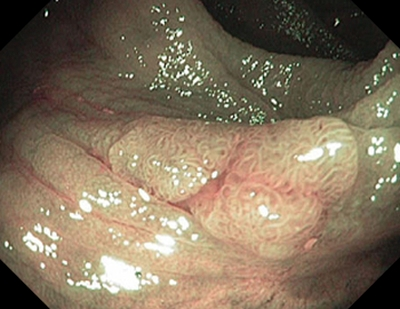

2 тип — характерний для аденоми

Колір: темніший (коричневіший), ніж навколишні

Судини: світліша ділянка в центрі, оточена більш товстими коричневими судинами

Поверхня: овальна, трубчаста, звивиста — наявність трубочок, лінійних або пучкових, світла ділянка в центрі, оточена коричневими судинами